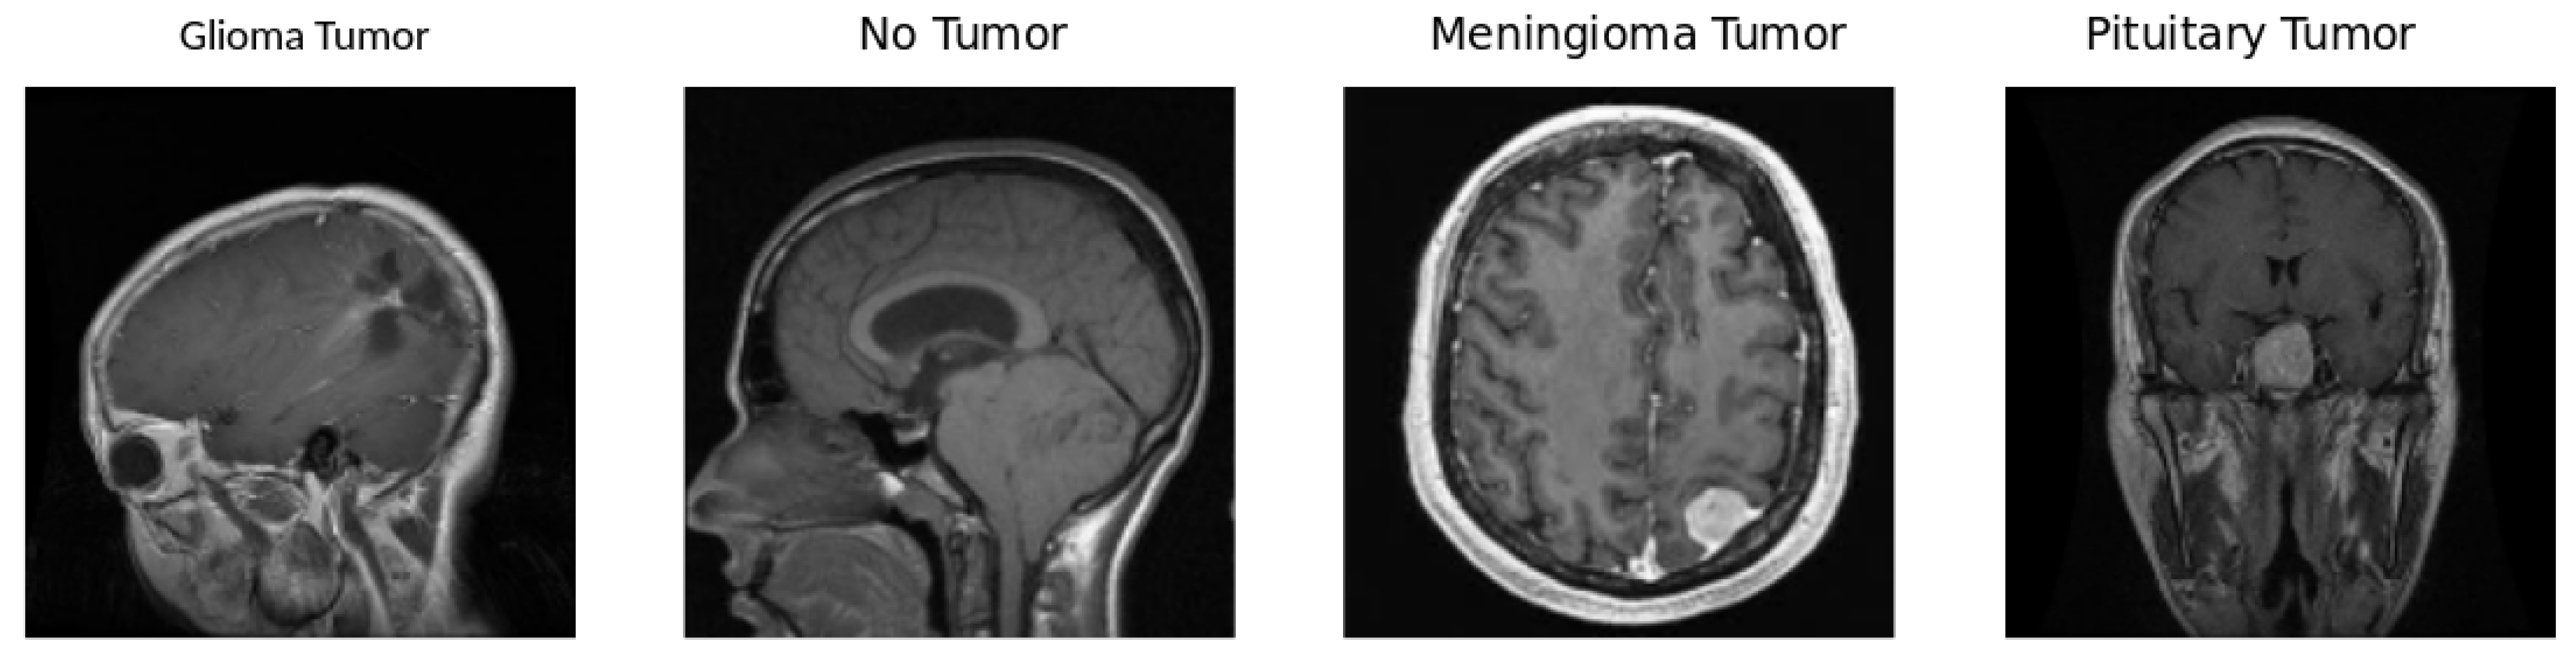

This brain tumor dataset comprises 3264 2D slices of T1-weighted contrast-enhanced images, encompassing three distinct types of brain tumors—glioma, meningioma, and pituitary tumors—along with images of a healthy brain. The dataset has been partitioned into 2937 images for training and 327 for testing purposes. Figure 1 visually presents samples from each of the four classes within the dataset and Figure 2 illustrates the proportion of each of the four classes in the dataset

Gliomas are tumors derived from glial cells and can manifest as either benign or malignant. Among them, glioblastoma multiforme stands out as a particularly aggressive variant, posing significant challenges in terms of therapeutic intervention [3]. Pituitary Tumors which arise in the pituitary gland, these tumors can disrupt hormonal balance. They may present as growths that secrete hormones or as non-functioning growths. Common sub-types include prolactinomas and growth hormone-secreting tumors, each with its distinct clinical implications. Meningiomas are generally benign, slow-growing tumors originating from the meninges. The symptoms associated with meningiomas vary based on the size and location of the tumor, making their clinical presentation diverse and often dependent on individual cases [3].

Figure 1. Sample of each image in the dataset. A Glioma Tumor image typically exhibits abnormal growth in the brain, indicating potential malignancy. No Tumor images represent a healthy state without any abnormal growth or lesions. Meningioma Tumor images showcase tumors arising from the meninges, the protective layers around the brain, and the spinal cord. Pituitary Tumor images depict tumors in the pituitary gland, influencing hormone regulation and potentially affecting various bodily functions.